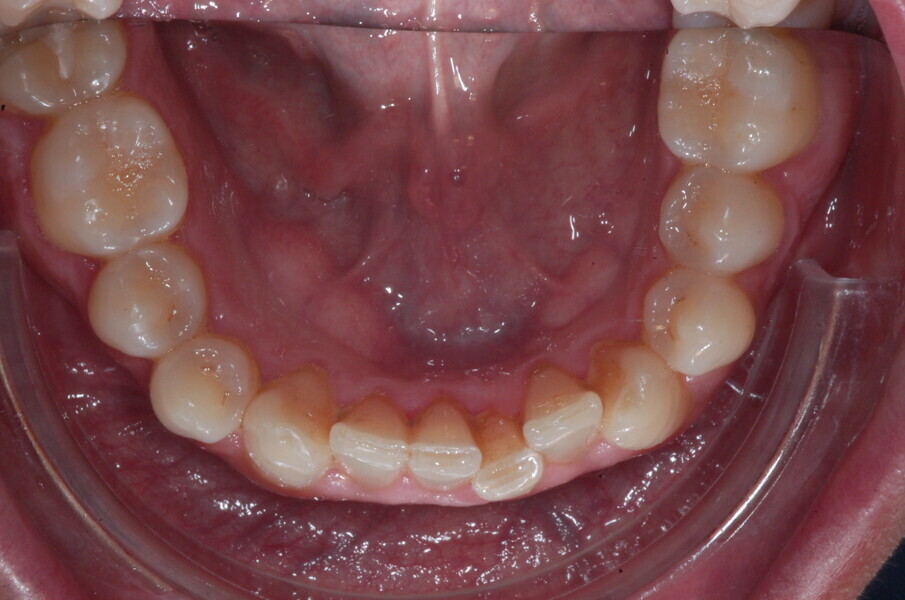

Le motif principal de consultation de ce patient âgé de 37 ans, était de rétablir l’alignement des dents antérieures sur les deux arcades. L’analyse faciale a indiqué une face courte avec un profil plat, mais une projection normale du menton (Figs. 9–12), et l’examen clinique a révélé une classe squelettique de type I (angle ANB = 0,89°) et une malocclusion de classe I avec supraclusion sévère (près de 100 %), une courbe de Spee très prononcée, un torque normal de l’incisive centrale supérieure (Ui-FH = 110°), un encombrement dentaire léger sur l’arcade maxillaire et modéré sur l’arcade mandibulaire (Figs. 13–18). Chez ce patient, les composantes de la supraclusion correspondaient à une dysmorphie squelettique grave correspondant à une hypodivergence (FMA = 14,24°), avec une inclinaison normale des incisives supérieures et inférieures et un angle goniaque réduit (110,46°). L’analyse du cliché céphalométrique indiquait une hauteur réduite de l’étage inférieur de la face associée à l’hypodivergence (Fig. 19). La seule option de traitement envisagée était un traitement orthodontique par aligneurs avec tous les éléments auxiliaires décrits (rampes d’occlusion, zones de pression, nivellement de la courbe de Spee dans les trois dimensions, élastiques de classe II et puissants contacts occlusaux) afin de corriger la supraclusion.

Le plan de traitement numérique (ClinCheck) avait prévu douze aligneurs pour l’arcade maxillaire et dix-sept pour l’arcade mandibulaire. Les objectifs du traitement visaient à combiner les mouvements verticaux d’extrusion des dents postérieures et les mouvements d’intrusion des dents antérieurs, au moyen de rampes d’occlusion, tout en utilisant des taquets d’extrusion pour assurer la désocclusion des dents postérieures et l’intrusion des dents antérieures inférieures, nécessaires au nivellement de l’arcade mandibulaire. La courbe de Spee a été nivelée et le profil plat ainsi que la position des lèvres ont été améliorés par une vestibulo-version des incisives supérieures et inférieures. Le plan avait prévu des élastiques de classe II pour faciliter la vestibulo-version des dents inférieures et les puissants contacts occlusaux postérieurs, avec une extrusion relative des dents postérieures. Une morphologie plus large de l’arcade et une intercuspidation idéale ont été obtenues par des mouvements de torque proches de 0° des dents latérales et postérieures supérieures. Aucune conception technique excessive n’avait été prévue dans le plan de traitement numérique. En raison de l’âge du patient, les aligneurs ont été changés tous les dix jours, dans le cadre d’un traitement d’une durée inférieure à six mois. À la fin de la première série d’aligneurs (Figs. 20–24), un nouveau plan de traitement numérique comportant cinq autres aligneurs a été conçu, en vue d’améliorer l’intercuspidation des molaires sans élastiques. La durée totale du traitement a donc été prolongée jusqu’à 7,5 mois puisque les aligneurs supplémentaires étaient changés toutes les semaines.